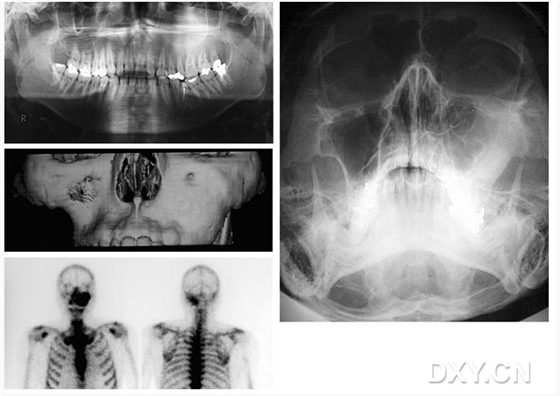

骨肉瘤

舍格倫綜合征

大理石骨?。ㄏ骂M骨有明顯的骨化影像,恒牙埋伏)

鼻竇炎(注意不要誤診呀)